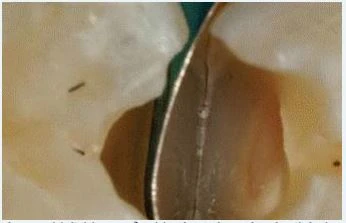

4. Trám lớp thứ nhất với GIC

Lớp GIC này cần thiết phải đủ độ dày, thật gọn gàng, có bề mặt phẳng mịn, tránh lem lên thành xoang, tránh tạo ra bọt khí và khoảng hở bên dưới miếng trám. Để đạt được các yêu cầu trên với dụng cụ trám thông thường đòi hỏi một bàn tay rất khéo léo, tuy nhiên để đơn giản hơn ta có thể tháo khuôn trám và mài chỉnh tạo hình lại xoang trám sau khi trám xong lớp GIC rồi đặt khuôn trám trở lại và thao tác tiếp các bước sau đó.